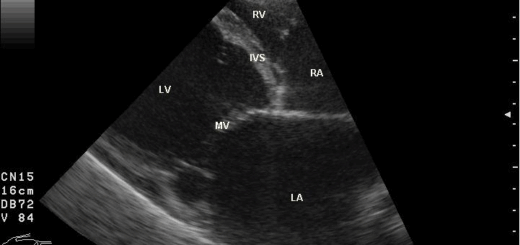

Week5 Day3 心臓の内景、スケッチ採点